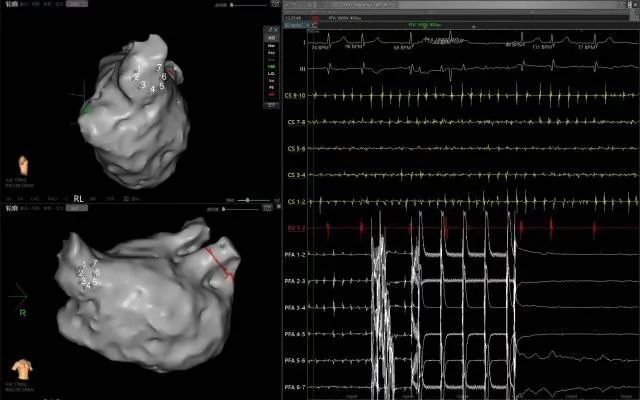

近日,延安大學咸陽醫(yī)院成功實施了咸陽地區(qū)首例脈沖場消融術、首例脈沖場消融+左心耳封堵“一站式”治療房顫手術2例手術的順利完成,標志著我院在心律失常治療技術上的又一重大突破!

此次手術患者均為持續(xù)性房顫患者,由延安大學咸陽醫(yī)院吳棟梁院長、心律失常專家劉雄濤副院長帶領介入團隊開展,安全高效、圓滿完成手術,手術過程患者全程清醒,術中自訴感覺良好,無痛苦感受。術后患者的心律恢復并維持了竇律,目前恢復情況良好,無任何并發(fā)癥出現。